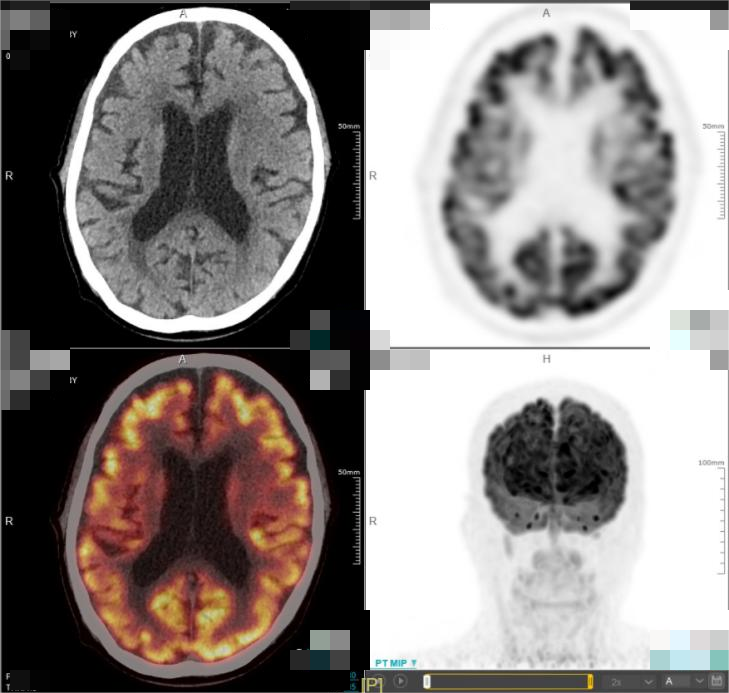

· 2025年5月,外院进行的头颅MRI检查结果显示,该患者的肿瘤再次进展。基于患者目前的疾病情况,中心医生先对其行全脑放疗,使用BTK抑制剂口服治疗,并且同步准备CAR-T细胞培养。此外,该患者还接受了氟达拉滨联合环磷酰胺方案进行预处理治疗,并于6月26日成功回输CD19 CAR-T细胞。在放疗后,患者的头颅MRI提示颅内病灶较前明显减少、减小。而CAR-T细胞治疗后50天复查PET-CT显示,患者的颅内肿瘤病灶已完全消失,达到完全代谢缓解(CMR)

图4.png图2. 患者 PET-CT结果(CAR-T细胞治疗后50天)